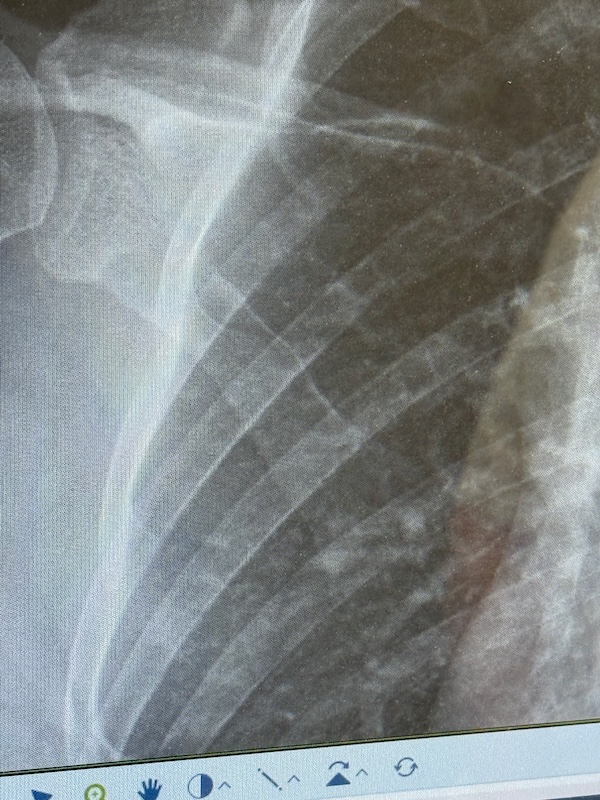

Ik zie Rob aankomen en pak mijn spullen. Het lukt allemaal, maar de pijn is groot. Ik kan door veel pijn heen, dat ben ik gewend, maar ik denk dat dit een verrekking is. Ik kan appen. Met links. We rijden naar de huisarts en wachten weer een kwartier. Ze ziet niks, maar mijn pijn is te groot. Ze denkt aan een pees scheurtje. Door voor een foto naar het ziekenhuis. De huisarts kent triatlon wel! In het ziekenhuis kan ik pas na 5 uur bij de huisartsenpost terecht voor een röntgenfoto. Even thuis langs voor een paar koekjes en wat drinken. Zelf een fles open maken lukt me niet. Rob appt en Vincent ook. Die gaat naar een terras. We zien een paar collega’s nog op de parkeerplaats: jo, jef en ma. Ik vind het ziekenhuis moeilijk. Ik haat deze plek. De huisartsenpost gaat net open. Ze lopen mee naar radiologie. Er worden 3 foto’s gemaakt. Ik mag mijn shirt aanhouden. En dan weer wachten. Ik moet de hele tijd plassen. En dat is lastig met 1 hand! Is dat een reactie van het lichaam, dat vele plassen? Er komen wat andere mensen; 1 meneer grapt dat hij zijn duim er met het stanleymes niet af kreeg. Ik snap die reactie wel: het heeft geen zin om te sippen, ik voel me ook nog vrolijkjes. Maar pijn hebben kost veel energie. Ik kan het echt allemaal minder goed snappen. Vincent komt ook. En dan worden we opgehaald. Na een uur. Ik raak het besef van tijd kwijt. Ze zegt: slecht nieuws he, dat ik je ophaal. Ik heb een breukje in mijn schouder. Dat komt hard aan. Zolang ik zat, voelde het beter. We lopen binnendoor naar de spoedeisende hulp. Er wordt verbouwd. Daar moet ik me melden. Een grappig vriendelijke mevrouw meldt dat het druk is en ik krijg een bandje. Tering, wat is er joh! Ze verifiëren mijn gegevens. Weer even wachten en dan een screening plek. Ze vragen wat ik heb gedaan en gokken op vallen met de fiets. Het is veel stommer dan dat! Ik leg ze uit en ze kijken even en ik krijg 2 paracetamols. Het dringt door dat dit lang gaat duren. Langer dan een week IJsselmuiden missen, zelfs mei lijkt afgeschreven. Pas als Rob en Vincent er bij komen vertellen we over triatlon. Weer een wachtkamer vol mensen. Ik kan het wel aan Vincent vertellen. Maar deze plek is nóg erger! Dokter Martijn haalt ons op. Hij laat de foto’s zien en gelukkig had ik Rob al gevraagd foto’s te maken van de foto’s.

Ik zie het niet zo heel goed. Ik hoor het: 3 weken niet sporten. Het moet weer aan elkaar groeien. Zelf. April en mei afschrijven. Geen triatlons. Binnen fietsen. Om wat conditie vast te houden. Niet hardlopen. Dat is zwaar voor een verslaafde! Over een week terugkomen. Ik krijg een sling. Ik update Jef en Ma en Jo zijn er bij en appen me ook. Joyce had ik al geappt voor de röntgenfoto. Die baalt met me mee. De dokter gaat vragen of een mri nog nodig is. Gelukkig niet. Ik krijg die sling, maar voor mij helpt het niet echt. Ik vraag hoe ik moet slapen en de dokter zegt: ogen dichtdoen 😆 ook over werken kan hij weinig zeggen. Ik ben blij dat er echt iets is en niet zomaar pijn. Maar ja, juist dat er iets is is erg pijnlijk. Hij helpt me met de sling, maar dat is vooral dat je ziet dat er iets is en dat rechts gefixeerd is. We lopen weer naar de auto en ik heb trek en pijn.  Dat het triatlonjaar voorbij is voor de eerste triatlon is pijnlijk. Ik heb mijn zorgbudget opgebruikt! We eten frietjes. Ik dek de tafel met links. MvdB belt me direct, de schat. De trainster is net even niet bereikbaar helaas. Ik bel de ouders. Ik had gelukkig de stappen gehaald. Rechtop zitten gaat nog het beste. Dat alle scherpte weg is merk ik wel bij het rummikuppen. Alsof ik er niet helemaal bij ben terwijl ik er erg van geniet. Ik schrijf het van me af. Op voor een lange nacht en het accepteren van een hoop verlies.

Ik heb mijn rechter schouderblad gebroken.

10 april. Een bedrijfsfeestje. Survivallen. Een stormbaan met een netje nog geen meter boven de grond. Ik ben verkeerd gevallen. Precies fout. Pijn, misselijkheid, toch maar naar de huisarts, foto’s in het ziekenhuis. De rest van april draag ik een sling om er voor te zorgen dat ik mijn rechterarm niet gebruik. De breuk moet zelf genezen. Met rust. Niet fietsen (al kan binnen wel), niet hardlopen en met zwemmen kan ik waarschijnlijk pas over 6 weken weer beginnen.

Uitleg gekregen: het schouderblad is inderdaad heel flink gebarsten zeg maar. Goed gebroken. Na 3 weken is het weer aangegroeid. Herstel tot wat ik kon kan tot een half jaar duren. Hij heeft het aangewezen en uitgelegd dat de frictie en wrijving pijnlijk is als ik mijn arm boven 90 graden til. Als hij het aanwijst, voel ik daar niks van. Het zit hoger dan ik dacht.

Wat ik niet kan is dus als die breuk langs de borstkas draait. Dan doet het zeer. Als ik dat toch doe, verergert de breuk niet.